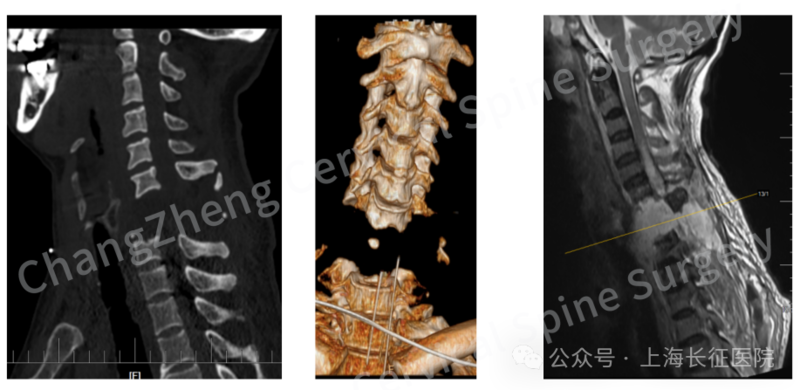

CT三维重建提示颈椎离断部位情况严重复杂

人共有两条椎动脉,分别位于颈部左右两侧。CT造影检查显示,患者的右侧椎动脉已经断裂,幸运的是正好被骨折软组织移位和血凝块堵住,椎动脉闭塞了。而左侧椎动脉遭到牵拉,“就像一根被拉长的细管”,勉强维持着血供。

据陈华江介绍,患者颈椎前后的骨和软组织全断了,面对如此严重的颈椎骨折脱位,单纯的颈椎前路手术钢板固定力量有限,需要采用颈椎后路,或前路联合后路手术进行复位固定。

尤为关键的是,团队创新性地应用了“卫星钢板”固定技术,在常规固定之外巧妙增加辅助钢板,为重建的颈椎提供了前所未有的超强稳定性,这一技术应用在此类极端病例中尚属首创。

团队创新性应用“卫星钢板”固定技术,为重建的颈椎提供了前所未有的超强稳定性